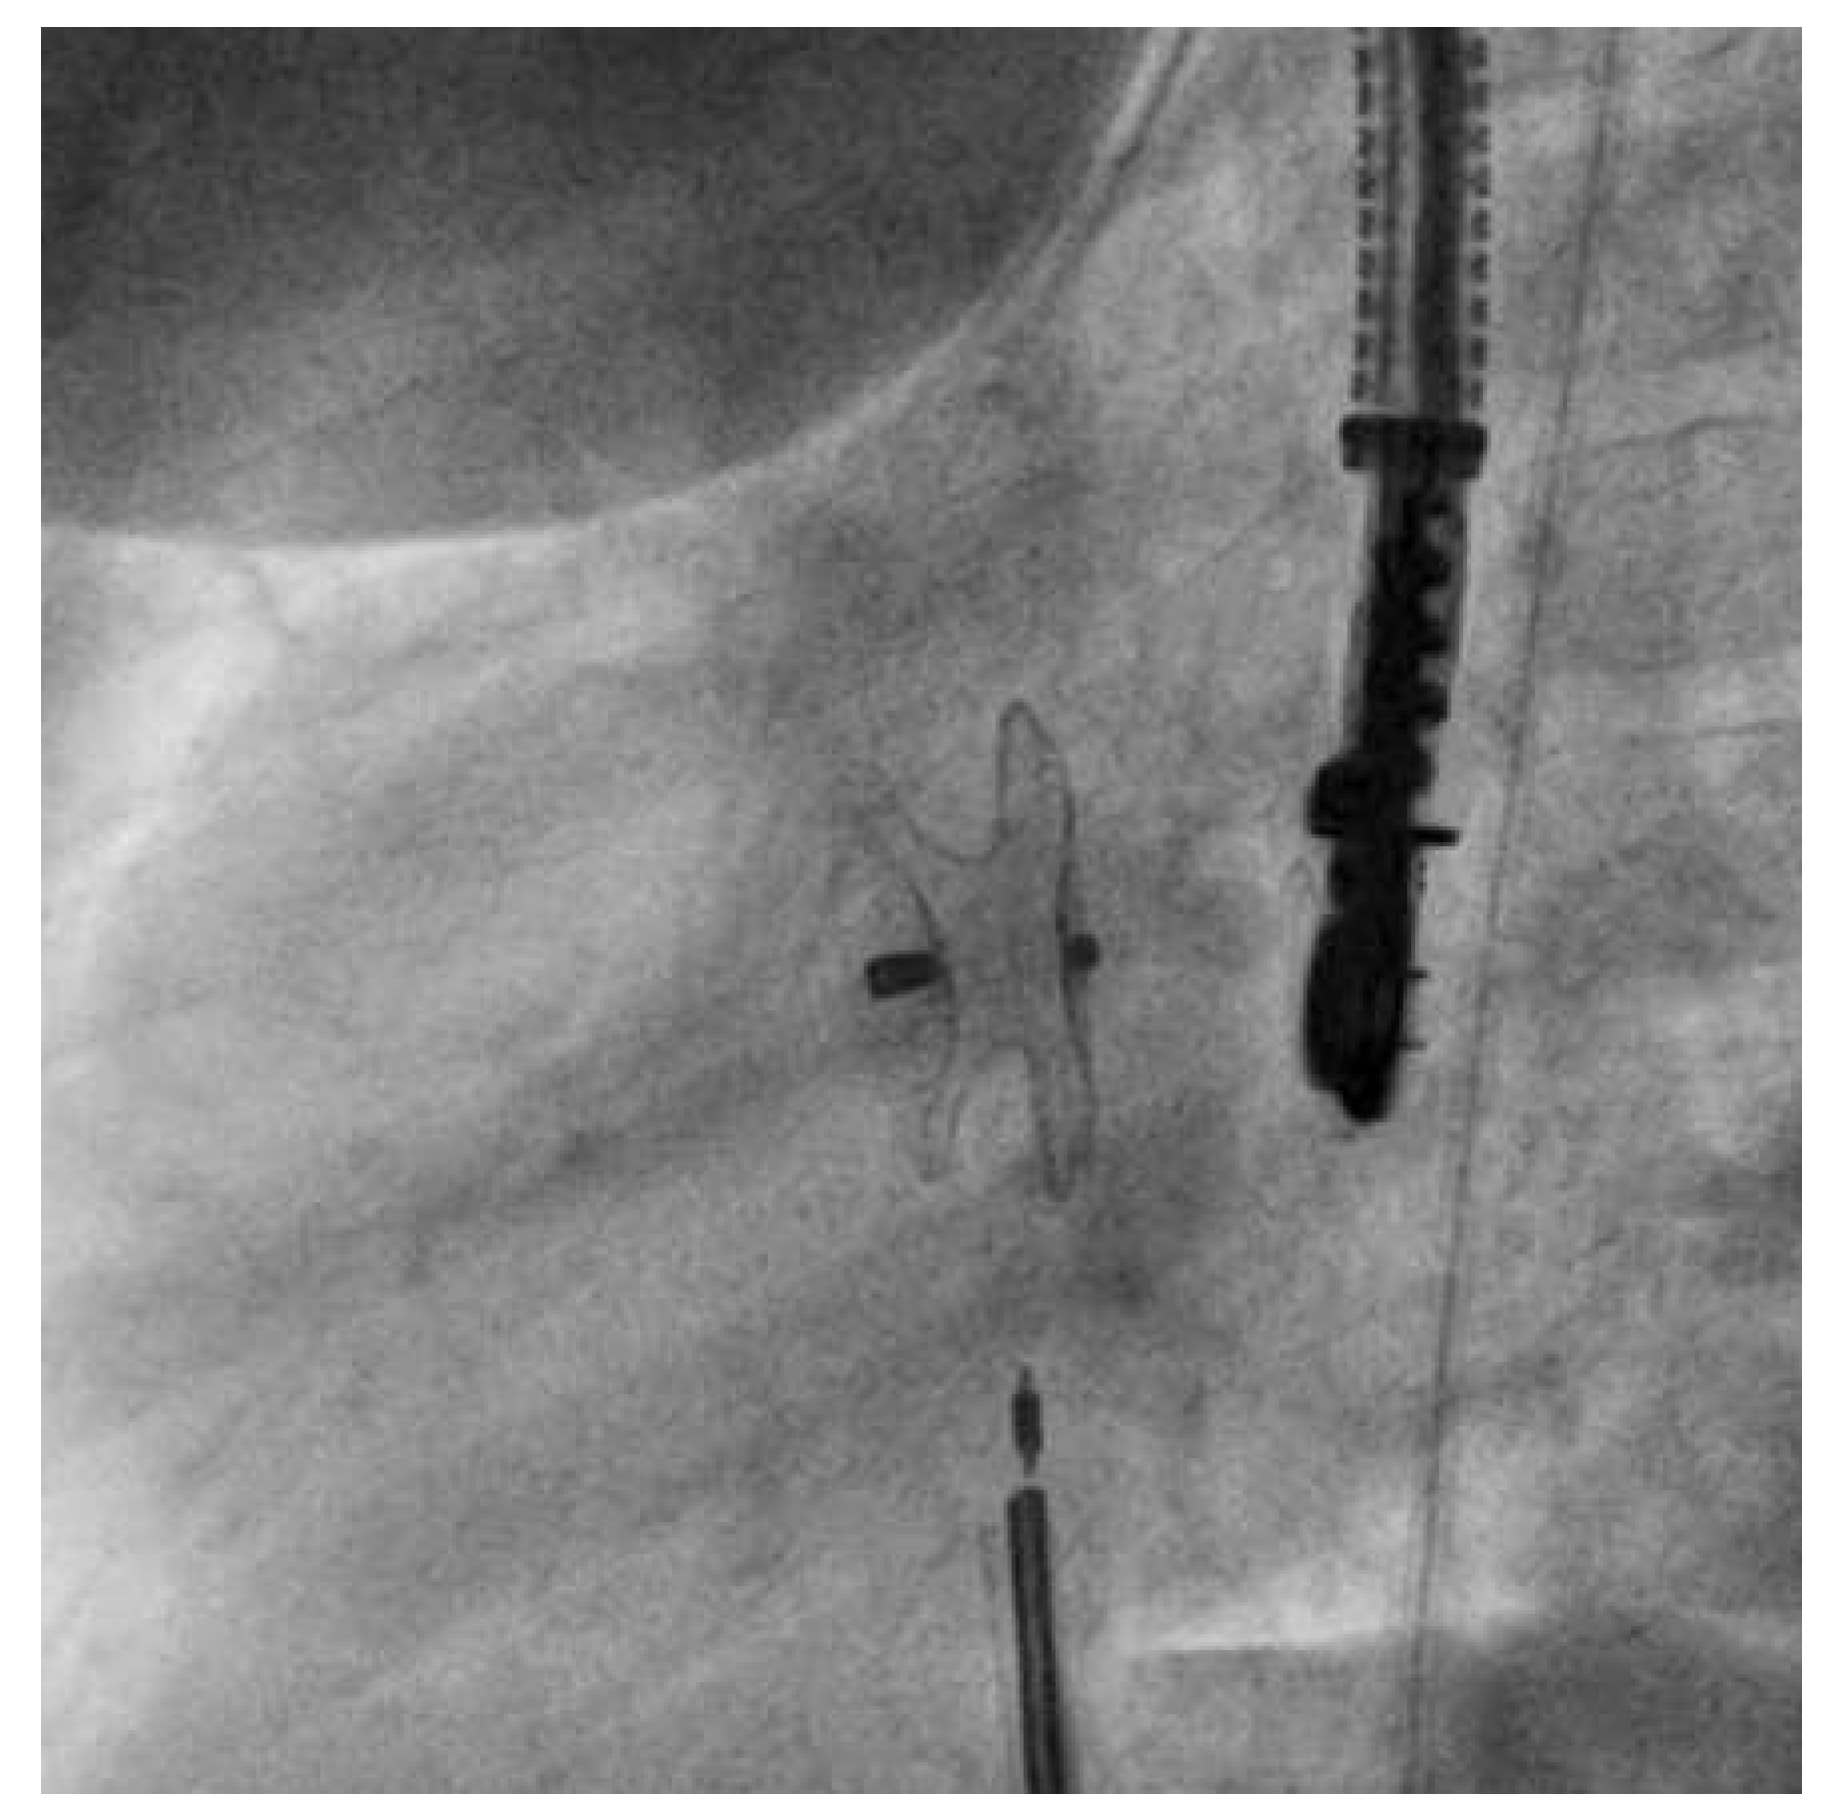

The procedure was conducted under general anaesthesia and fluoroscopic guidance combined with transoesophageal echocardiography monitoring. Aher tracheal intubation, venous access was gained through the right femoral vein with a 6 French CheckFlow introducer set and the patient was treated with 1 000 units of intravenous unfractionated heparin and 900 mg of intravenous cefuroxime. The atrial defect was passed under fluoroscopic guidance with a 4 French multipurpose catheter. A stiff guidewire was placed in the leh superior pulmonary vein. A 14-mm Hyperion Atrial Septal occluder (Comed) was chosen on the basis of the findings of echocardiography and balloon sizing (24-mm Amplatzer sizing balloon, St. Jude Medical, Plymouth, USA). We decided to close the defect with 14-mm Hyperion Atrial Septal Occluder (Comed). The 6 French introducer sheath was exchanged for a 10 French delivery Hyperion sheath (Comed) and advanced into the leh atrium. The preassembled Hyperion occluder was loaded and the leh atrial disc of the occluder was opened. Aherwards, the delivery sheath and the disc were retracted as a unit until the disc hugged the septum. Subsequently, the right atrial disc was opened in the right atrium. At this stage, the HyperionFlexPusher cable allowed for retraction of its stiff sleeve with the device remaining attached to the screw at the end of the core wire. This relieves the distortion by relaxing the tension of the system. The device position achieved came close to the final position with the precise orientation to the atrial septum (Figure 1, video 1). At this point, the device could still be retrieved and redeployed or replaced. The device was then released by counterclockwise torquing the core wire (Figure 2, video 2). Ideally, the stiff sleeve should be readvanced at least partially before that to avoid entangling of the flexible core wire during torquing. The patient was discharged on the following day aher a TTE and chest X-ray had confirmed good device position. Acetylsalicylic acid (100 mg per day) was recommended for 6 months.

Figure 2. Video 2. After releasing the device (left anterior oblique 72° / caudal 12° projection).